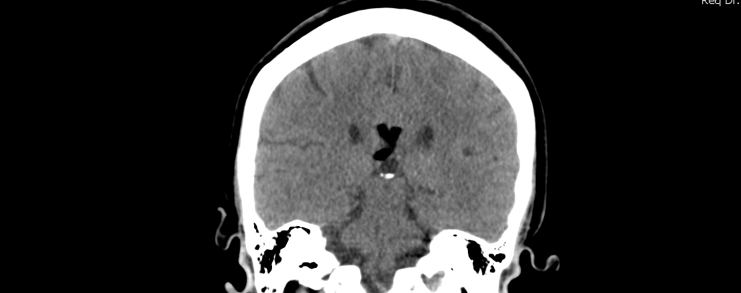

What’s that CT finding?

Can you identify the abnormality on this head CT?